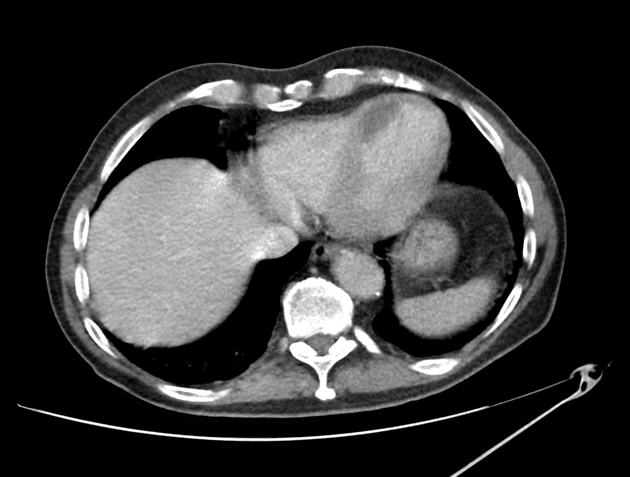

Salut les amis 🎉 Homme, 78 ans, post-SCA. Scanner car douleur abdominale, des coupes passent au niveau du thorax. Que voyez-vous ? 🌐 Interprétation : https://t.co/klcvSsNL84 #Radiologie #EDN